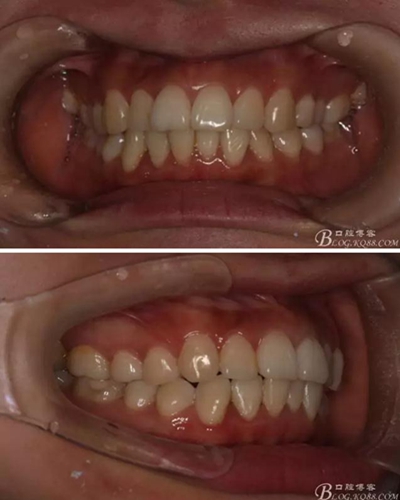

患者,女,主訴:牙齒不齊。

如圖,該病例為簡單排齊病例,但77鎖合是矯治中的關(guān)鍵所在,你會怎么處理?

該病例主要為17、27頰側(cè)位同時伴有伸長,當(dāng)然種植支抗可以解決,但還有簡單實用的辦法嗎?如圖,在橫腭桿遠中延伸出牽引鉤,位置盡量遠離合平面,7粘舌側(cè)扣,牽引力的方向為壓低及舌向,下圖為兩個月的效果,17已到位,27還未到位。